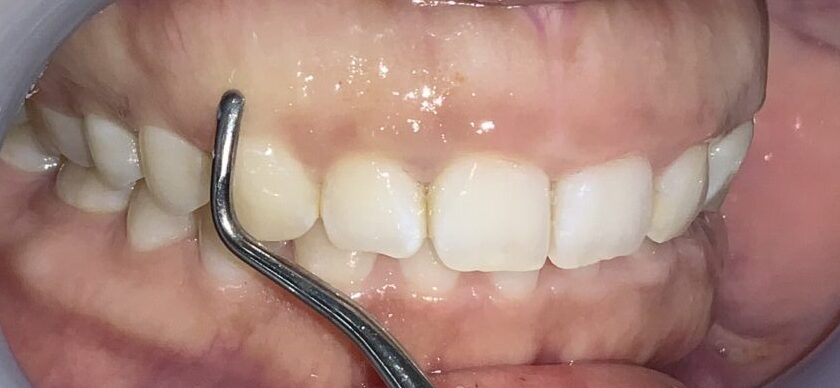

今回の患者様の治療前の状態です。

歯ぐきの長さに比較して、歯が少し小さいですね。歯ぐき自体は健康で綺麗なピンク色をしています。

一番気になる、前歯の歯と歯ぐきの位置状態の検査します。

こんなに歯ぐきがかぶさっています。